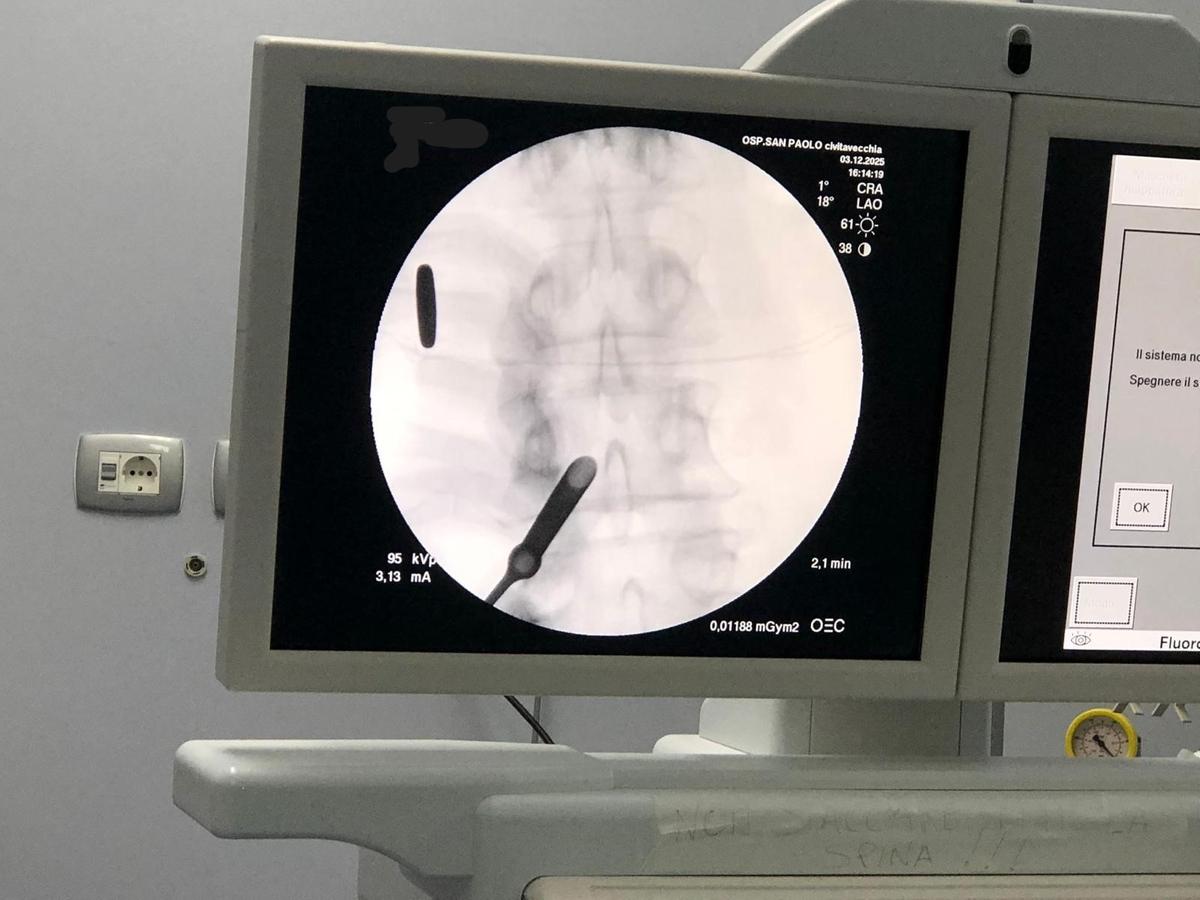

«Nel nostro Centro di Terapia del Dolore – spiega Amorizzo – stiamo utilizzando una nuova tecnica endoscopica minimamente invasiva per il trattamento della stenosi del canale vertebrale, una patologia molto diffusa soprattutto nella popolazione oltre i 60 anni e tra le principali cause di dolore e perdita di autonomia».

Questa procedura, eseguita tramite una micro-endoscopia con accesso percutaneo, permette di decomprimere selettivamente il canale vertebrale senza un’apertura completa e senza ricorrere a chirurgia tradizionale, riducendo drasticamente: tempo operatorio, complicanze, tempi di recupero e necessità di ricovero.

Parliamo ad esempio proprio della stenosi del canale vertebrale, procedura che viene effettuata con tecnica micro-endoscopica di circa 7 mm, una procedura in anestesia locale e in day hospital che non richiede riabilitazione post operatoria in modo che il paziente possa rapidamente ritornare alla sua vita sociale.